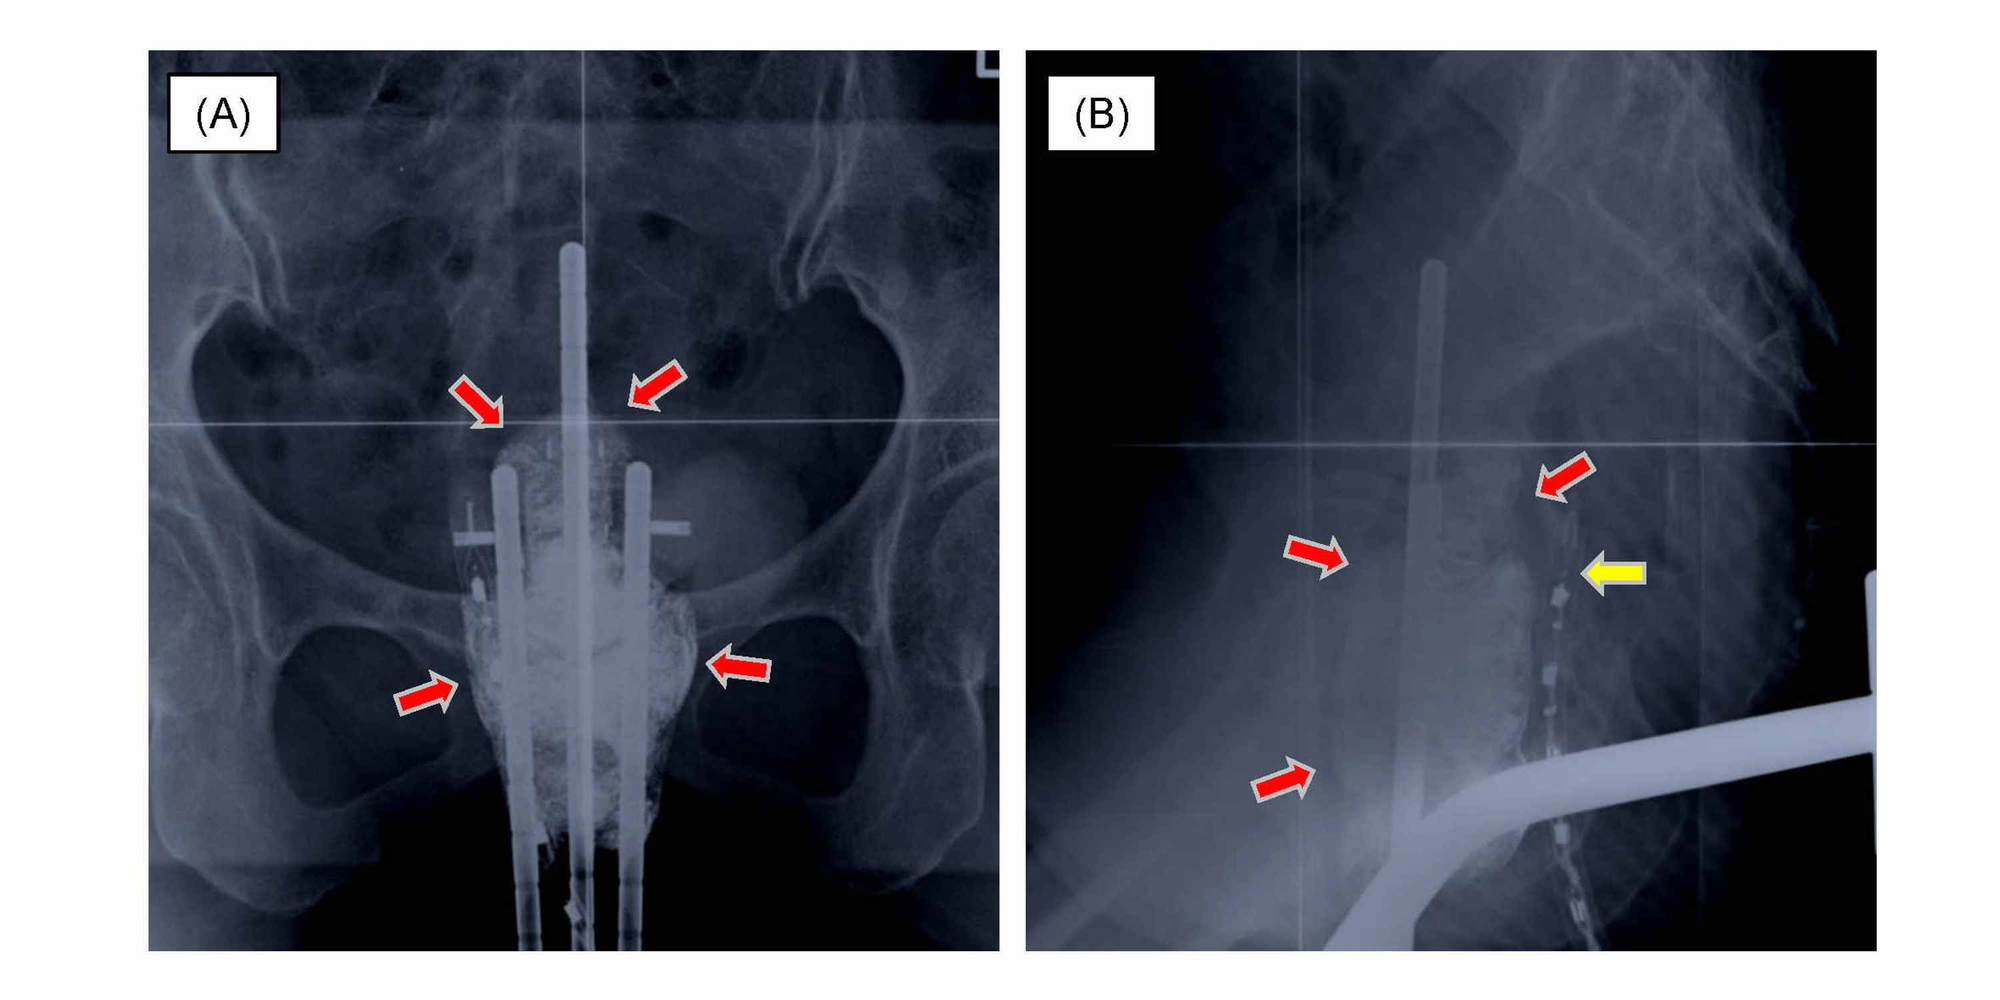

Cureus Vaginal Fistulas of the Bladder and Small Bowel After Two Brachytherapy Applicators Cervical Cancer to present recommendations for the use of imaging for evaluation and procedural guidance of brachytherapy for. brachytherapy provides high doses of radiation to the cervix, while sparing nearby organs at risk from high doses of radiation. Design, application, treatment planning, and dosimetric results brachytherapy (bt) delivers integrated boost doses to the central tumor while sparing the surrounding. Brachytherapy Applicators Cervical Cancer.

Figure 2 from Aiming for 100 Local Control in Locally Advanced